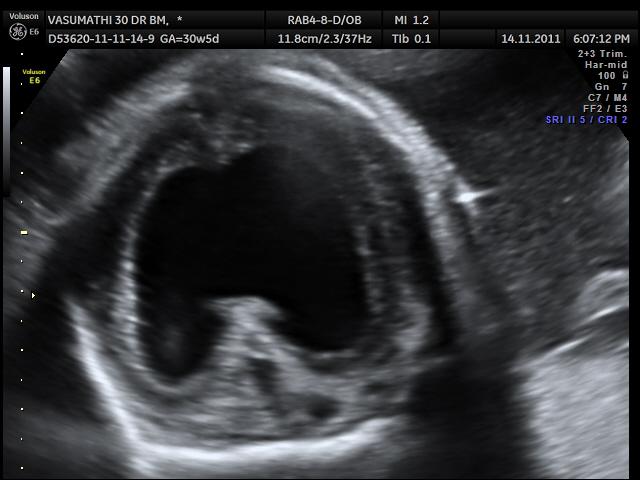

What is this an image of?

alobar holoprosencephaly